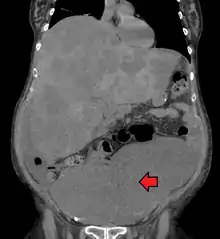

Colon cancer with extensive metastases to the liver

Colorectal cancer diagnosis is performed by sampling of areas of the colon suspicious for possible tumor development, typically during colonoscopy or sigmoidoscopy, depending on the location of the lesion.[20] It is confirmed by microscopical examination of a tissue sample.

Medical imaging

A colorectal cancer is sometimes initially discovered on CT scan.[81]

Presence of metastases is determined by a CT scan of the chest, abdomen and pelvis.[20] Other potential imaging tests such as PET and MRI may be used in certain cases.[20] MRI is particularly useful to determine local stage of the tumor and to plan the optimal surgical approach.[81]